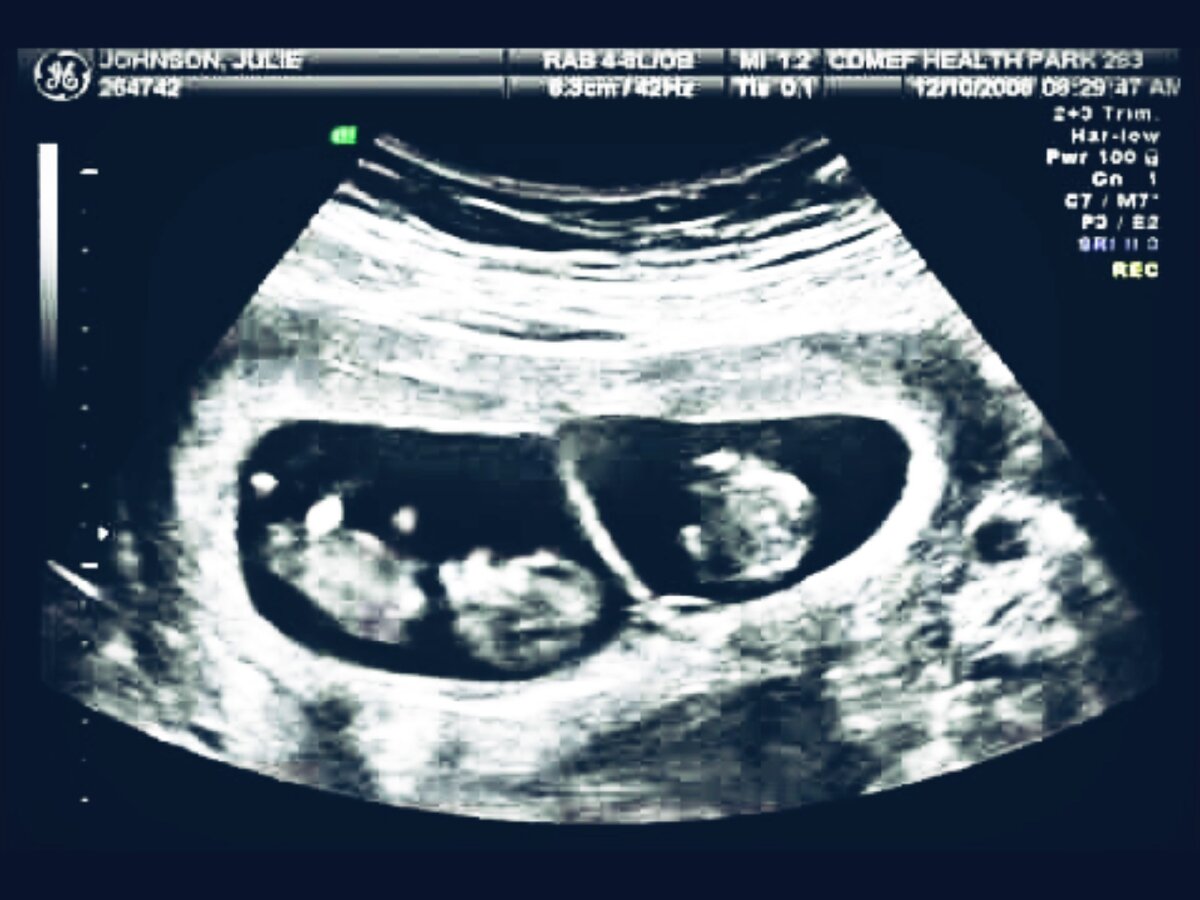

"Двойня в животе", Врач отказывается принимать роды.

Долго не получалось забеременеть, и вот свершилось. Беременность. Все счастливы, муж носит на руках. На 7 неделе выясняется, что я жду двойню. Замечательно. Все ещё более счастливы, хотя врач намекает, что двойню выносить сложно, бывают осложнения. Но мы верим в лучшее. Беременность первая, долгожданная, надо обязательно наблюдаться у самого

Долго не получалось забеременеть, и вот свершилось. Беременность. Все счастливы, муж носит на руках. На 7 неделе выясняется, что я жду двойню. Замечательно. Все ещё более счастливы, хотя врач намекает, что двойню выносить сложно, бывают осложнения. Но мы верим в лучшее. Беременность первая, долгожданная, надо обязательно наблюдаться у самого лучшего врача, а желательно потом ещё и рожать с ним же. Долго читала рекомендации, отзывы. Нашла. Самый лучший, лучшие рекомендации, лучшая статистика, perfect! Дорогой, правда, но никаких денег не жалко. Сходили к нему на консультацию. Все, говорит, хорошо, только вот двойня...

Чудо-доктор говорит, что стоит лечь на сохранение, подготовиться к кесареву, да и двойня, как правило, раньше рождается. Ок. В 35 недель я на сохранении. Жду назначения планового кесарева. Настроена на операцию. Приходит на обход профессор, и говорит, что для кесарева нет показаний. Да, двойня, но показаний нет, будете рожать естественным путём) А как же летальность? А статистика? А родовые травмы?